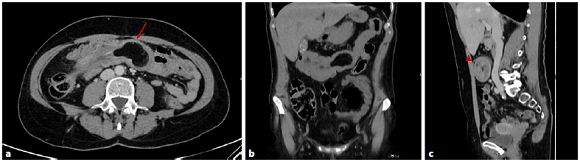

Due to persistent and intense abdominal pain, she was admitted to the emergency department, and an abdominal CT scan was performed, which showed a homogeneous lesion with fat density in the transverse colon lumen, measuring 5 × 3,5 cm, suggestive of a colonic lipoma (Fig. 2a). Moreover, proximal to the mass, a “donut”-like image was identified, establishing the diagnosis of colocolic intussusception due to the presence of a colonic lipoma (Fig. 2b, c). There were no bowel distension, hidroaeric levels, or other evidence of obstruction. The laboratorial study was unremarkable.

Fig. 2 CT image in axial (a), coronal (b), and sagittal (c) views showing an endoluminal homogeneous fat density lesion, located in the transverse colon (arrow), that corresponds to a colonic lipoma. Proximal to the mass, a “donut”-like image is identified (arrowhead), and the colonic lumen is filled with mesenteric fat and blood vessels. The findings are consistent with a colocolic intussusception.